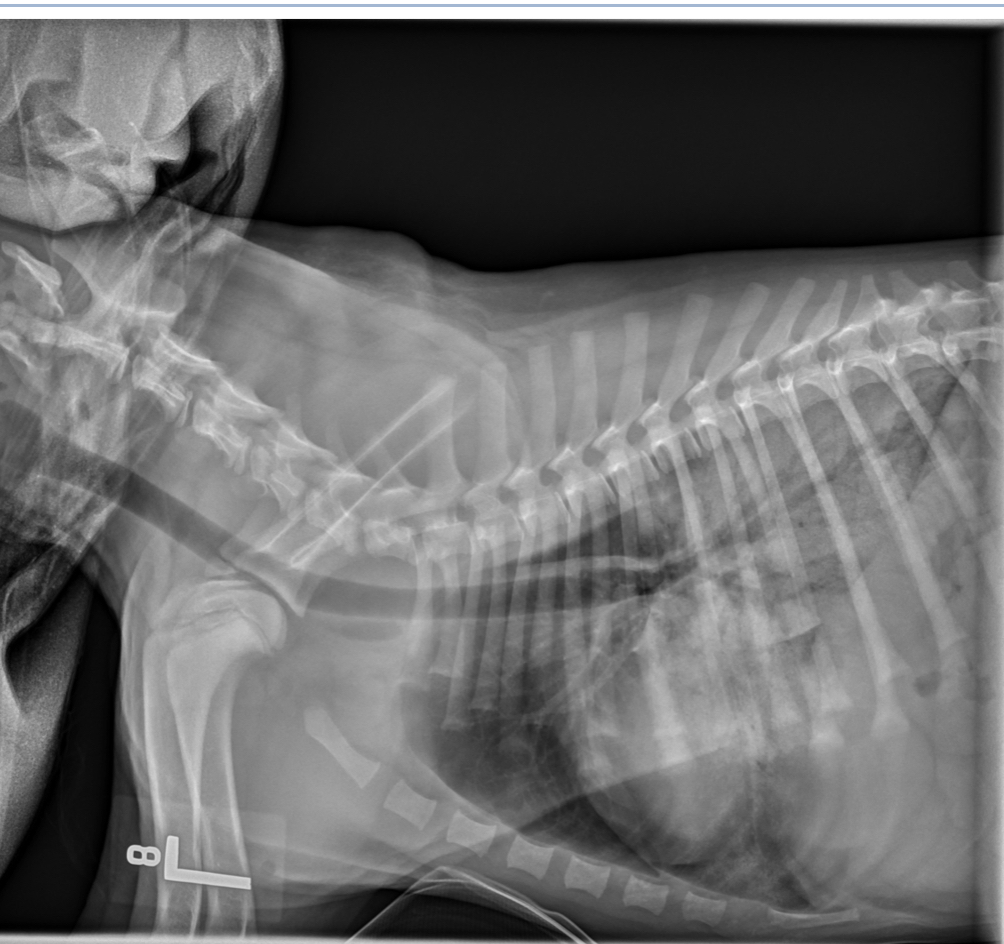

Q

1 month old leonberger presented with distress and lethargy. What wrong

A

peritoneal-pericardial diaphragmatic hernia